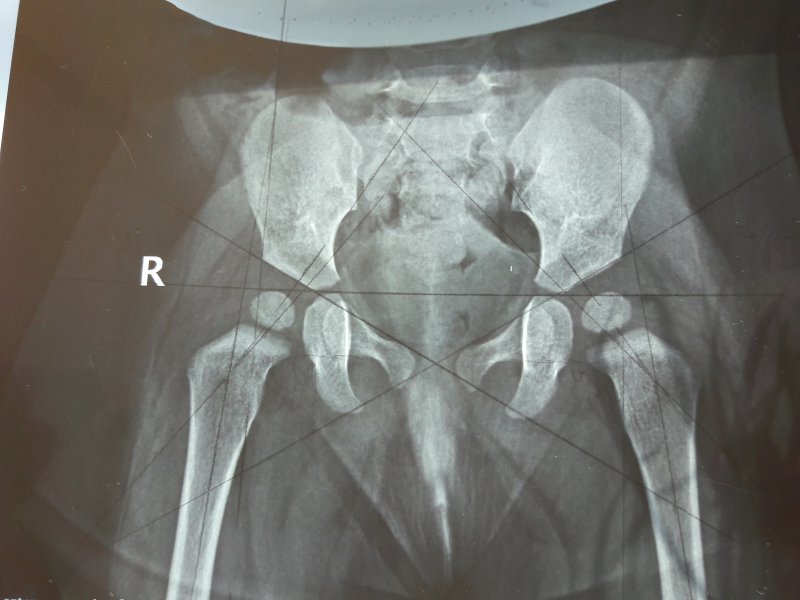

Оссификация тазобедренных суставов: что это и как проявляется?